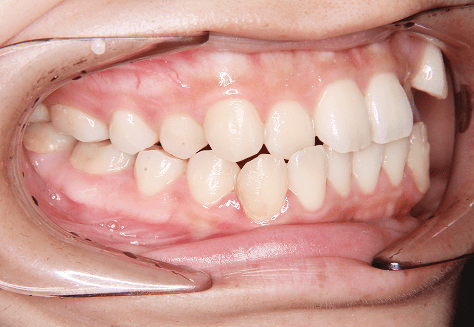

M.H

治療前

治療後

主訴

前歯が出ている。下の歯並びが特に気になる。奥歯でしっかり噛めない。

診断

上顎前突・叢生・シザーズバイト

年齢/性別

20代/男性

抜歯部位

下顎両側大三大臼歯(口腔外科にて)

上顎両側第一小臼歯・下顎左側側切歯

(当院にて5,500円×3) -

使用装置

上下エッジワイズ→インビザライン(PBM使用)

保定装置

上下ビベラリテーナー

料金

初回資料採得・・・・・・・30,000円

診断料・・・・・・・・・・33,000円

動的治療終了時資料採得・・5,500円 -

基本料金

880,000円

診察料金

5,500円×44回

治療期間

3年6カ月